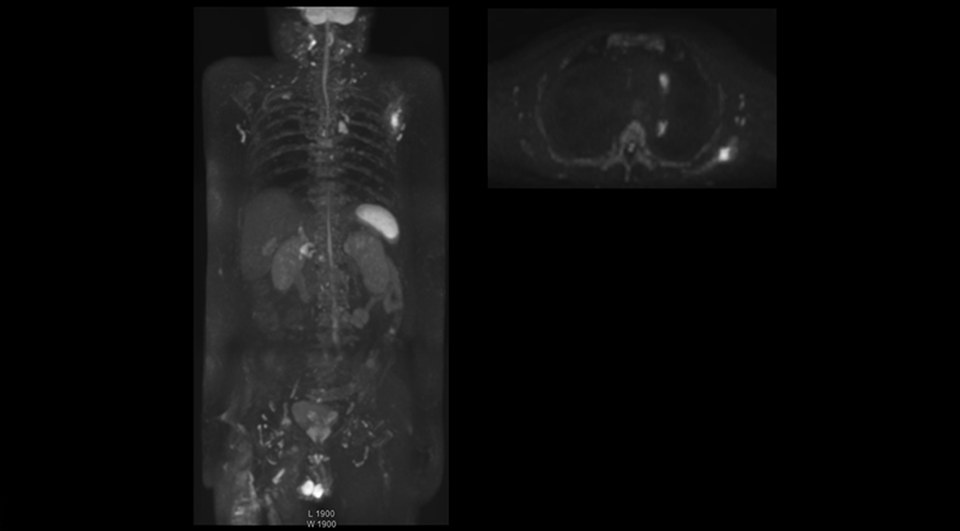

Kawasaki Sawai Hospital’s whole body protocol also includes an mDIXON FFE sequence. Because mDIXON provides images for four contrast types – water only, fat only, in-phase and out-of-phase – from a single acquisition, it is useful in many ways.

“mDIXON FFE allows us to quickly get information we need to assess the presence of fat. That gives us more information when we need to diagnose bone lesions, and when we are asked to judge fat-containing lesions such as hepatocellular or renal carcinoma,” Dr. Nobusawa says.

“The mDIXON fat images can help us to differentiate fatty bone marrow from bone lesions. This is especially useful in elderly people, who tend to have fattier bone marrow. The water images provide a high signal-to-noise ratio in the intestinal canal, which is valuable for visualizing lesions in the colon,” he says.

“In-phase and out-phase sagittal T1-weighted FFE images help us to visualize and further characterize bone lesions such as metastasis and bone-marrow hyperplasia that have high signal on DWI. These images are also used throughout radiotherapy, to monitor changes in the fatty bone marrow.”